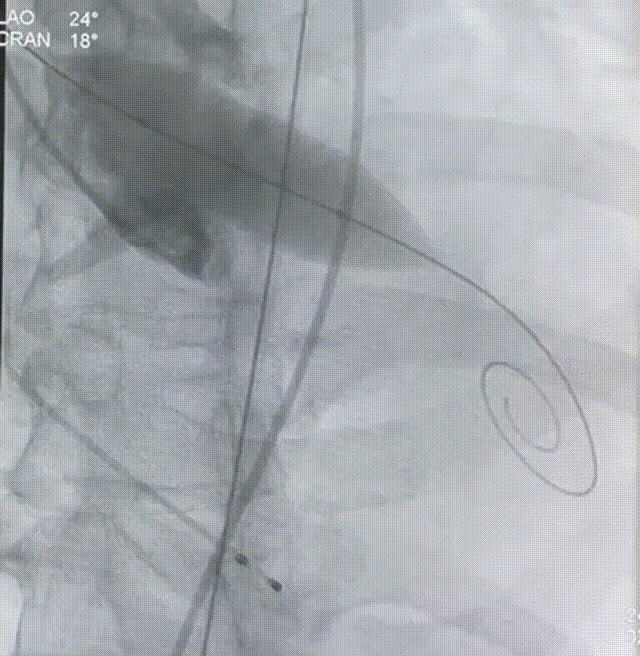

主动脉根部造影

入路情况

双侧入路CT测量

入路双侧血管迂曲